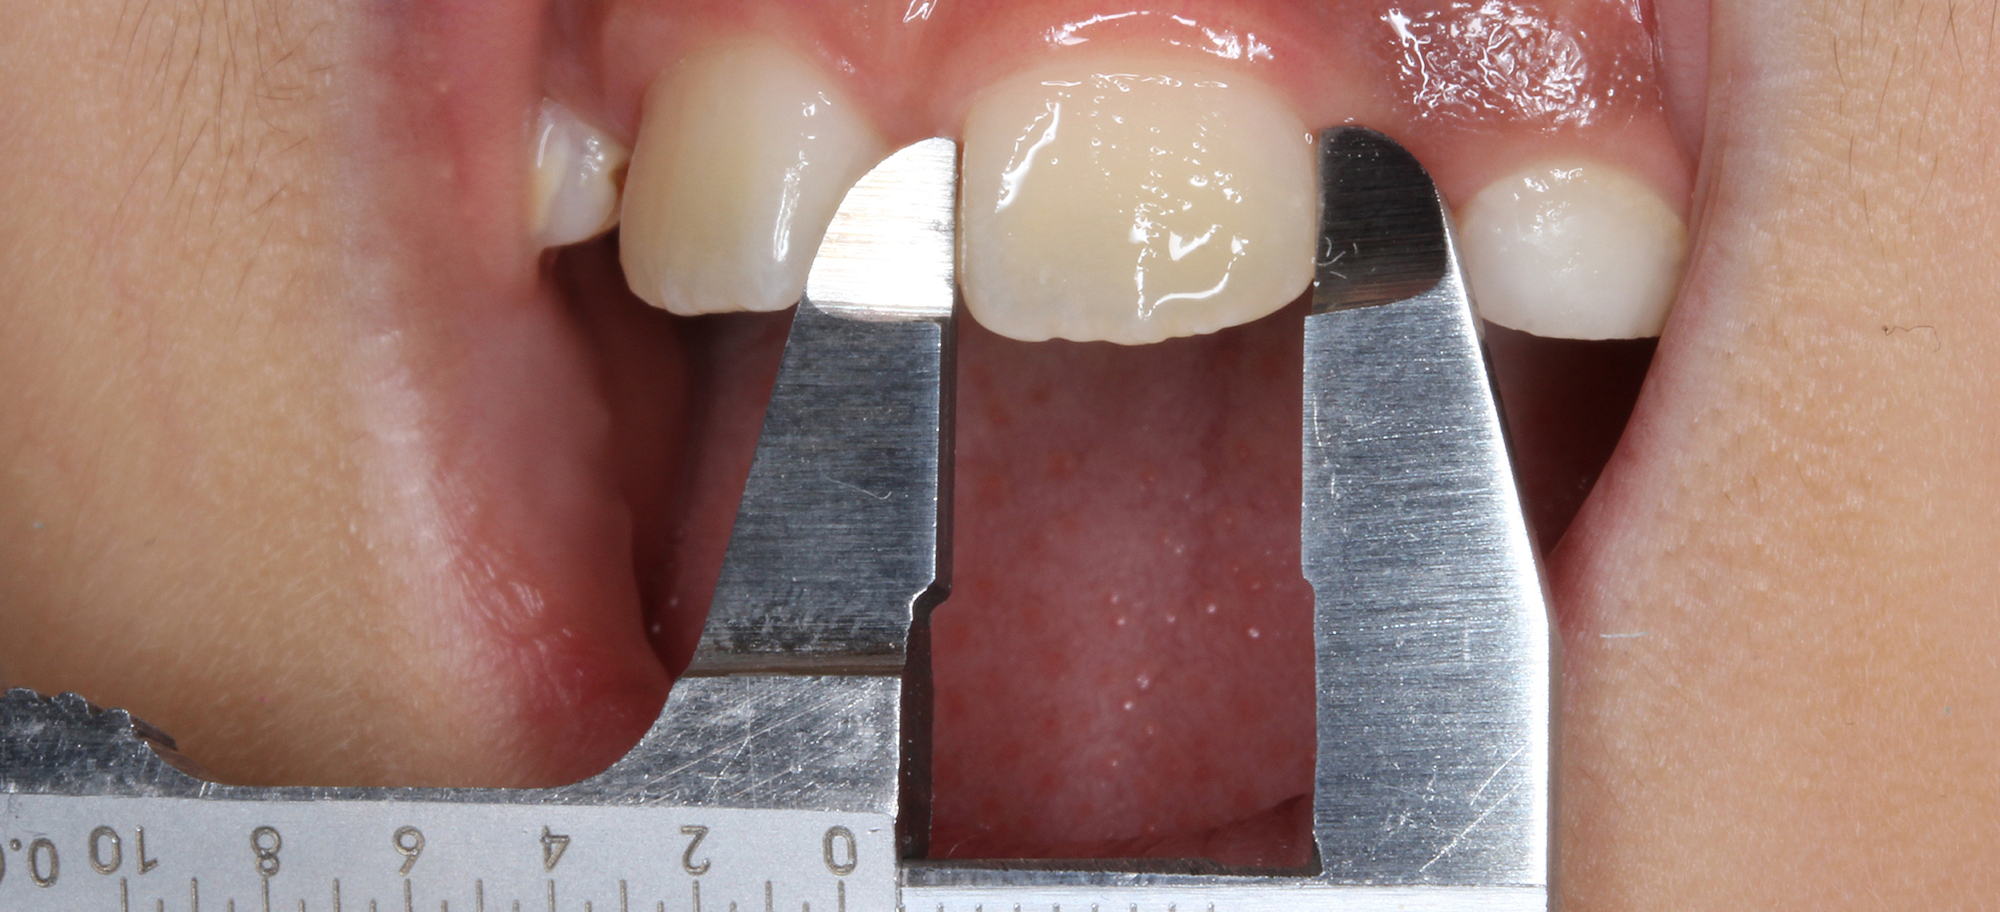

日本で行われている拡大床治療にも色々な方法がありますが当院での特長は最初に永久歯に生え替わる上下4本の前歯を奥歯の生え替わりが始まる前までに顎を拡大してきれいに並べることです。そのため拡大床治療の期間は小学校1年生頃から4、5年生頃までの間に限定しており、それまでに目的が達成できない場合には別の治療法に移行します。またゆっくりスペースを獲得するようにしているのも特長で2週間に1回ネジを回すようにしています。一般的には1週間にⅠ回ないし2回ネジを回すことが多いようです。ゆっくり進めるので一日の装着時間はお家にいるときと寝ている間だけにしています。学校や自宅以外での装着はせずゆっくり拡大していくので治療期間が長くなりますが後戻りは少なく確実になります。治療開始時期が大切ですので時期を逸した場合には拡大床治療は行いません。一般的に拡大床治療の評判が悪いのは開始時期が遅く、いつまでも治療を長引かせ治らないことによるものが多いようです。 拡大床治療はスペースを作って永久歯がならぶスペースを作ることが目標ですので細かい歯の向きや角度まで整えられないこともあります。そんな場合には別の矯正治療が必要になります。

拡大床治療ではすべての歯がきれいに並ぶように顎の成長を促すことが目的ですので細かい歯の位置や角度までは調整できません。また歯が大き過ぎる場合には口の中で歯が目立ちすぎることになる場合もあります。日本人を含めたアジア系の骨格には特長があり、ヨーロッパ系の顔立ちとは基本的に違っていますが上下の歯を抜いたりすることでそれに近づけることもできます。矯正専門の歯科ではそのような目標を立てて治療を行うことが多く、そのために4本の永久歯を抜歯することもあります。拡大床治療では歯を抜かずすべての自分の歯でしっかり噛めることを目標にしていますので口元のきれいさを目的にする治療とは異なります。歯を抜いて口元をきれいにするのは大人になってもできる治療ですので、親としては先ずはお子さんのすべての歯を使ってきれいに歯をならべることを優先すべきで、あとで本人が口元が気になるというのであれば本人の意志で歯を抜いて矯正治療を行うべきであるというのが当院の考えです。